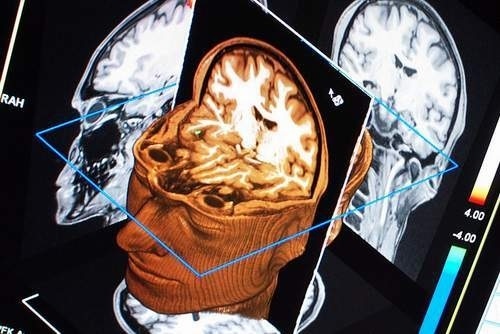

Old  Default Bí ẩn: Sau cú ngã chấn thương sọ não trở thành nhà tiên tri

Ông Peter Van Der Hurkos sau khi bị ngã chấn thương sọ não bất ngờ có năng lực phi thường như tiên tri nhìn thấy trước vận mệnh của mình và người khác.

Những trường hợp nêu trên cho thấy Hurkos có được năng lực tiên tri sau lần bị chấn thương sọ não năm 1941. Tài năng của Hurkos thuyết phục được cảnh sát châu Âu và Mỹ và họ đã mời ông cộng tác.